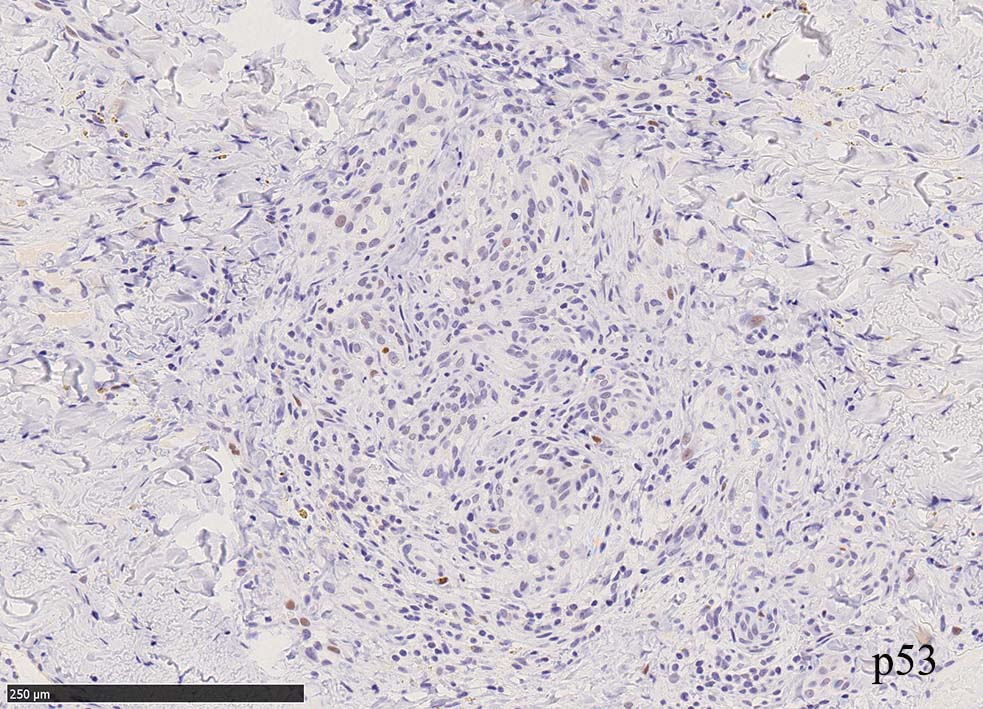

紡錘形細胞が著しく増生し束状に走行する部分と, 内皮細胞様細胞による多数の小管腔構造が巣状にひろがり, 一見, 線維腫と血管腫が混在しているように見える. 一部の症例を除き, これらの増生細胞は異型性に乏しいことが多い.

免疫染色, 分子病理学的検査

増生細胞はCD31, CD34, Factor Ⅷ, D2-40などが陽性を示す.

HHV-8の潜伏期関連抗原(HHV-8 Latency-associated nuclear antigen: HHV-8 LANA)が市販されており, 核が点状に染色される陽性所見がKaposi肉腫の確定診断に必須となっている.